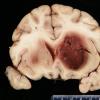

1B2 Artifact, frozen half medulla (L) into formalin without thawing vs fixed (R) (Case 2) H&E 4 whole mount